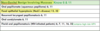

What are these radiographic findings?

Residual Cysts

What is the radiographic finding?

Residual Cyst

Residual Cyst

Etiology

- After tooth extracted, not properly cleaned ► the residual cells of the cyst lining and inflammatory cells continue to proliferate

- Has to be at site where tooth was previously removed

Residual Cyst

Radigraphically

- well defined round to oval radiolucency in the site of a previous extraction

Residual Cyst

Histologically is identical to which cyst?

- identical to the radicular cyst (periapical cyst)

- Should biopsy to rule out other causes